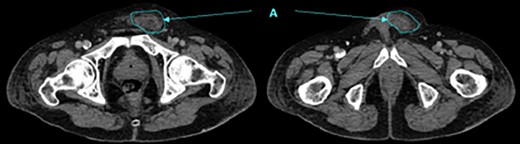

Contrast CT showing fluid tracking anteriorly into the left inguinal region (A).

A laparoscopic cholecystectomy and open hernia repair was planned. During surgery a pancreatic abscess was discovered with fluid tracking within the left inguinal canal. The left groin abscess was drained; however, the spermatic cord and cremaster were grossly implicated resulting in the need for a left orchidectomy. Post-operative CT scans showed a decrease in the inflammatory changes in the peripancreatic fat, in keeping with resolving pancreatitis.